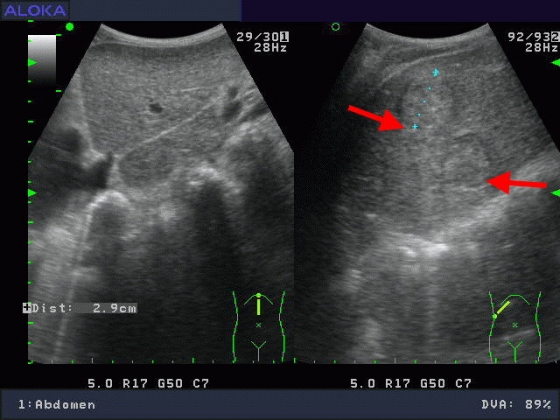

醫學影像..腹部超音波 :肝臟

肝硬化